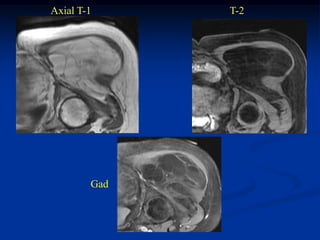

Case #281.2                        Synovial lipoma knee

Axial

T-1                                T-2

Gad

48 year old female with

tender lump over medial